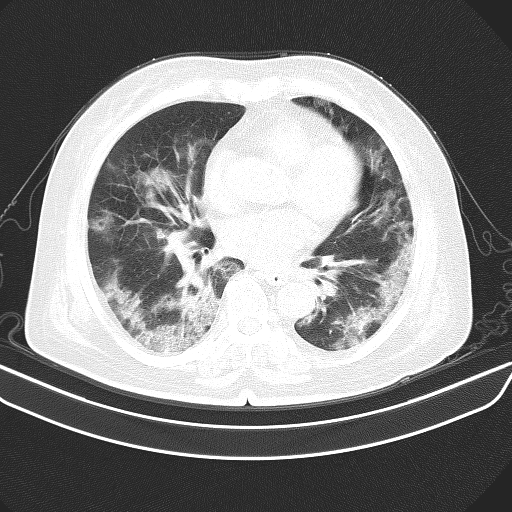

The proposed COVIDNet-CT was pre-trained on the ImageNet [36] dataset and then trained on the COVIDx-CT dataset via stochastic gradient descent with momentum [37]. The hyperparameters used for training are as follows: learning rate=5e-3, momentum=0.9, number of epochs=17, batch size=8. Data augmentation was applied with the following augmentation types: cropping box jitter, rotation, horizontal and vertical shear, horizontal flip, and intensity shift and scaling. In initial experiments, it was found via explainability-driven performance validation (see Section 3.5 for more details on the methodology) that erroneous indicators in the CT images (e.g., patient tables of the CT scanners, imaging artifacts, etc.) were being leveraged by the network to make predictions. To help prevent this behaviour, we introduce an additional augmentation which removes any visual indicators which lie outside of the patient’s body, as illustrated in Figure 5. Finally, we adopt a batch re-balancing strategy similar to that employed in [18] to ensure a balanced distribution of each infection type at the batch level. The proposed COVIDNet-CT was implemented, trained, and evaluated using the TensorFlow deep learning library [38].

Figure 5: Example COVID-19 case before and after removal of irrelevant visual indicators as part of data augmentation. In (a), a number of irrelevant visual indicators are present, such as the patient table of the CT scanner as well as imaging artifacts. After removing these irrelevant indicators, the image in (b) is obtained.